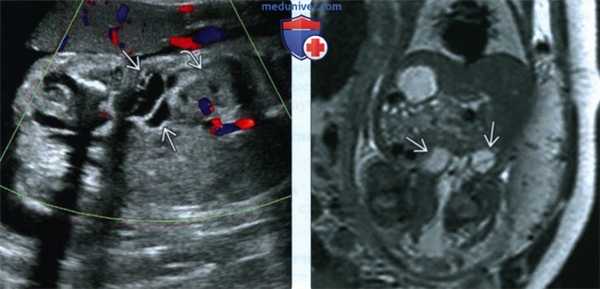

(Слева) УЗИ таза и брюшной полости плода, фронтальная плоскость. СКТВ с поражением нижней конечности. Образование распространяется в забрюшинное пространство до уровня почек.

(Справа) Тот же плод. МРТ, Т2-ВИ. Глубина распространения образования внутрь туловища визуализируется более отчетливо.

3. МРТ при синдроме Клиппеля-Треноне-Вебера у плода:

• Наилучшим образом позволяет визуализировать глубокие поражения:

о Уточнение анатомической локализации:

- Поражение кишечника

- Поражение других органов

о Для оценки распространенности поражений выполняют МРТ